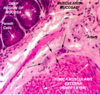

Loose Connective Tissue, Skin, Upper Lip

The marker is on a fibroblast. As you can see, the cell is beneath the epithelium and surrounded by a pink loose substance. What is this substance? Does the fibroblast produce it?

tissue?

The tissue is skeletal muscle. The structure is the orbicularis oris facial muscle.